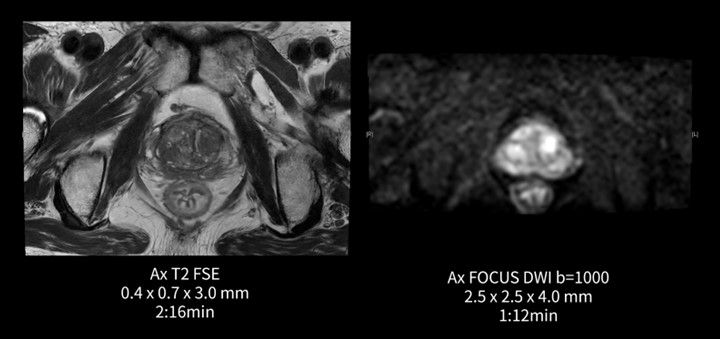

前立腺(前立腺癌疑い)

当院では、2021年よりPI-RADSの撮像条件に準じたものに変更した。以前より面内の分解能を細かく、スライス厚を薄くしたため、3TといえどもSNRを担保するため時間をかけて撮像していたが、AIR™ Recon DLによってその悩みは解消された。例として、T2強調像は3分47秒→2分16秒に、FOCUS DWI b=1000は3分0秒→1分12秒と大幅に撮像時間の短縮となった。

図5.前立腺(前立腺癌疑い)